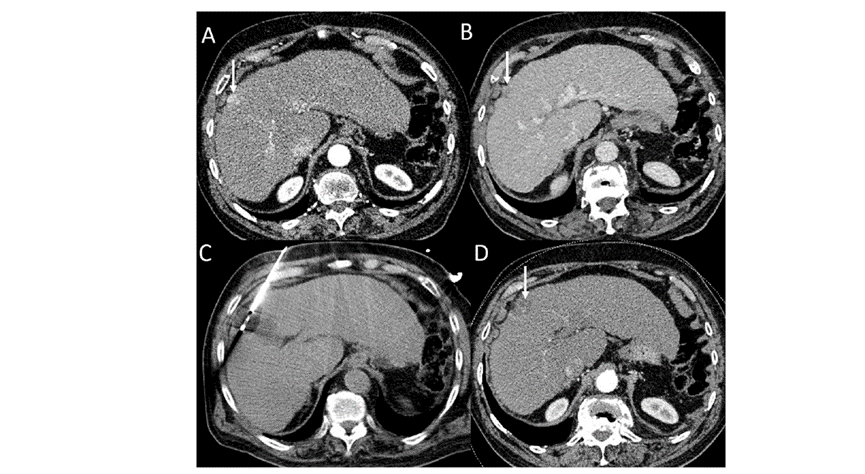

(A)動脈期CT圖像顯示有一個包膜下結(jié)節(jié)(箭頭)。(B)門靜脈期CT圖像顯示病灶區(qū)(箭頭)。(C) 在手術(shù)過程中的CT顯示一個冷凍探針位于病灶內(nèi)。(D)消融后,術(shù)后1個月影像CT顯示完全消融。患者在手術(shù)及住院期間無并發(fā)癥及重大并發(fā)癥發(fā)生。隨訪時間中位數(shù)為7個月(范圍:3-12個月),隨訪期間患者無局部腫瘤進展或死亡。

技術(shù)成功率為100%,本研究中77.8%(7/9)的患者達(dá)到了完全消融,輔助局部治療后,所有患者均完全消融。

膽囊附近轉(zhuǎn)移灶(來自子宮頸癌)的冷凍消融術(shù)(A)門靜脈期 CT 圖像顯示膽囊附近有病變(箭頭)。(C) 手術(shù)過程中CT 顯示冷凍探針位于病灶內(nèi)。(D)消融手術(shù)后 1 個月CT 顯示完全消融。

本研究中患者隨訪期間無局部腫瘤進展,無死亡病例,沒有發(fā)現(xiàn)與手術(shù)相關(guān)的并發(fā)癥。證實冷凍消融是一種有效的治療方式,在技術(shù)上是可行和安全的。由于肝包膜下病變位置特殊,射頻消融有出血及腫瘤種植的風(fēng)險,可能會對鄰近器官造成損傷,并且增加局部腫瘤進展的風(fēng)險。近年來,冷凍消融術(shù)的應(yīng)用逐漸廣泛,有研究顯示冷凍消融治療具有明顯優(yōu)勢,可治療特殊部位的肝腫瘤。本研究的目的是評價冷凍消融治療肝包膜下腫瘤的安全性和有效性。回顧性納入2016年7月1日至2018年9月1日期間冷凍消融的57例患者。包括42例男性和15例女性,平均年齡為62.4歲(范圍:48-82歲)。每個患者有1個或2個平均腫瘤尺寸為2.4cm的病變(范圍:0.6-4.0cm)。所有患者均患有慢性肝病或肝硬化,并伴有乙型肝炎(n=52)、丙型肝炎(n=3)和其他肝炎(n=2)。根據(jù)腫瘤位置,在膈肌或肝臟下附近有18個病變(26.5%),胃或腸附近有9個病變(13.2%),腹壁附近有33個病變(48.5%),腎臟附近有8個病變(11.8%)。